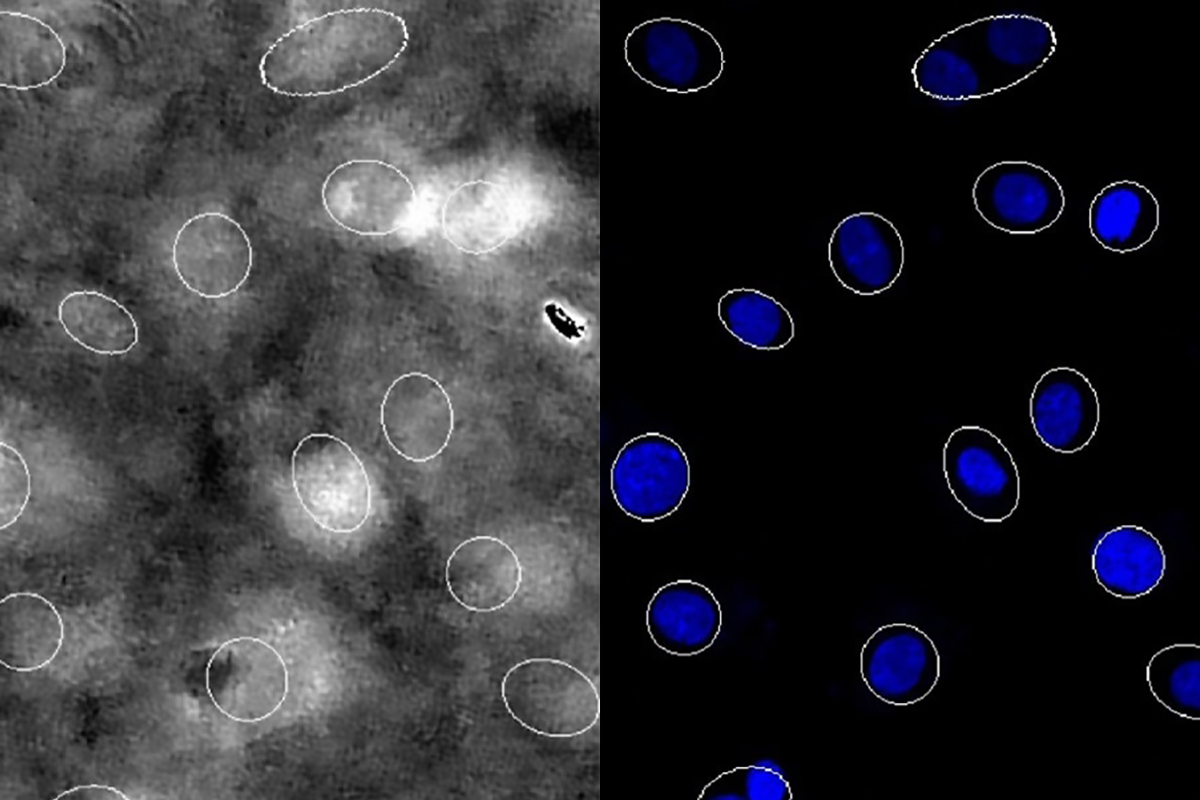

Precision robotics offers hope for heart disease treatment

The advanced drug testing system screens multiple potential therapies simultaneously in beating heart cells.